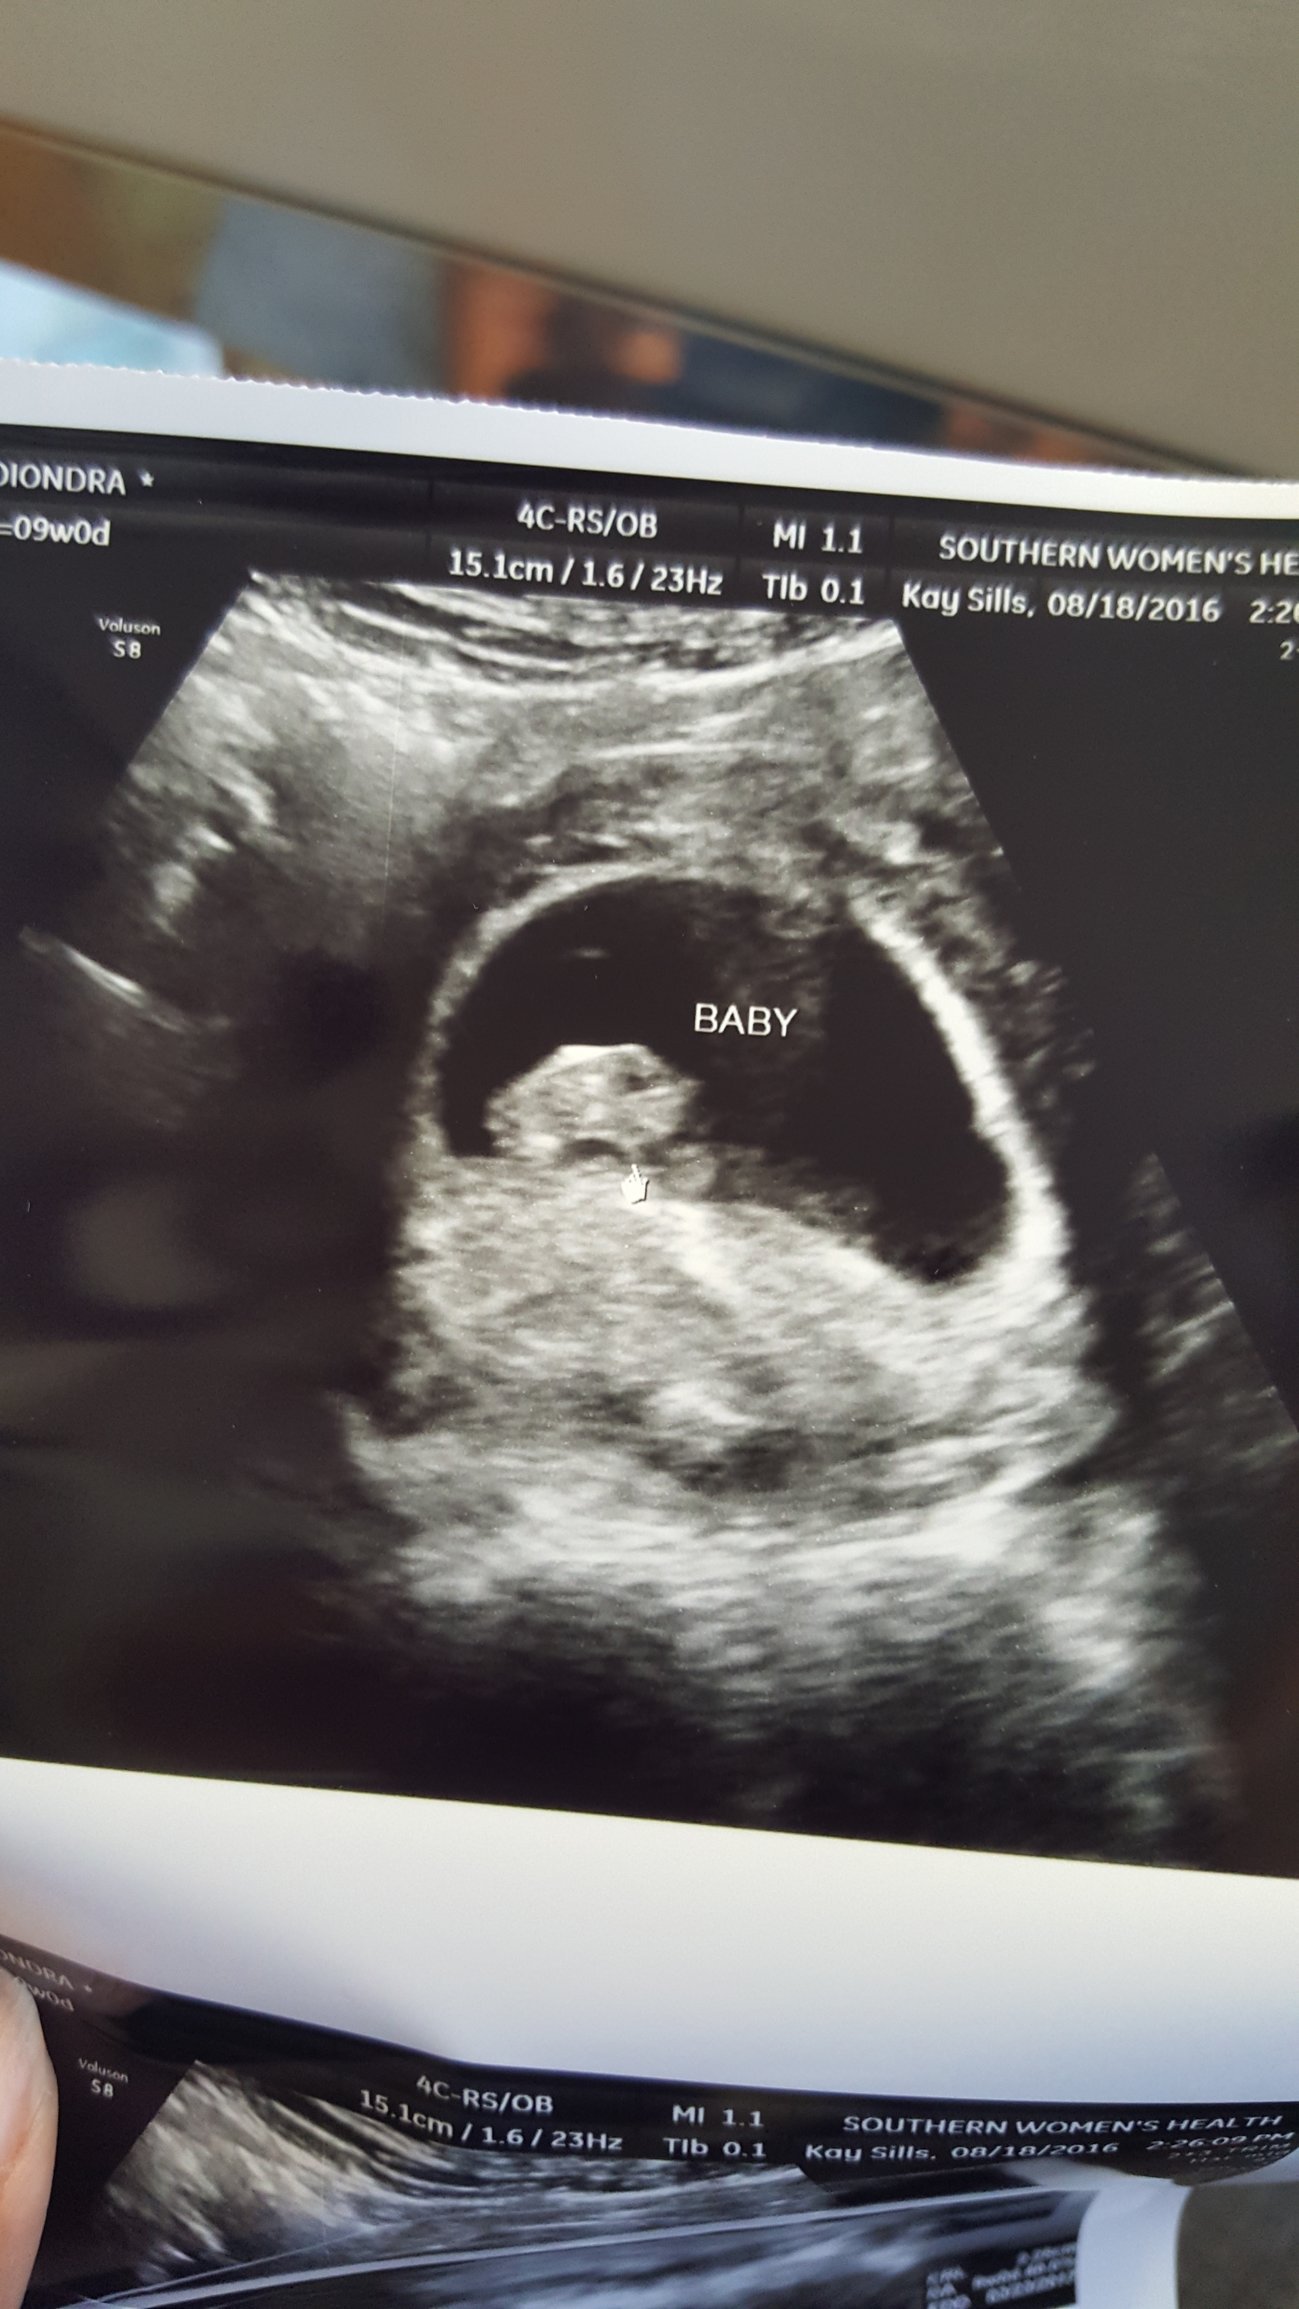

I'm cautiously announcing our pregnancy to some boards at this time. We will be 11 weeks on Friday. It has taken us FIVE years to get to this point - yes FIVE. We have had 8 miscarriages and 1 ectopic. We have been monitored pretty closely this time and have had an ultrasound every week to date. We are praying this is our take home baby.

Our due date is March 9th. I'm really excited to get to know everyone over here. I'm mostly a lurker and don't spend too much time online (work full time, our six year old is starting school again soon, etc etc). However sometimes it is really nice to have another group of people in the same situation with the same goals and fears.